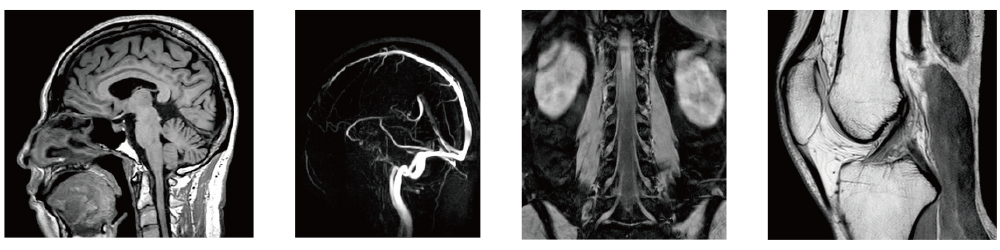

GUI Cardíaca AutoPose

AutoPose Pélvis Feminina

AutoPose Joelho

Foi desenvolvida uma tecnologia para converter dados extensos de TC acumulados através do SYNAPSE 3D em imagens de RM usando a tecnologia de IA. Esta tecnologia, combinada com uma biblioteca de rede neural convolucional (CNN) estabelecida durante o desenvolvimento da segmentação de órgãos, foi usada no desenvolvimento do posicionamento de RM. Como resultado, foram comercializadas capacidades de posicionamento de alta precisão para diversas regiões anatômicas.

A função de suporte à configuração da linha de corte, "AutoPose", define automaticamente as linhas de corte assim que o escanograma é digitalizado.

Após a conclusão da imagem de ressonância magnética, ele realiza automaticamente o recorte para MRA cerebral. O recorte automático identifica o intervalo de extração com base nas características da cabeça. Recortes adicionais também podem ser feitos nas imagens após o processo do recorte automático.